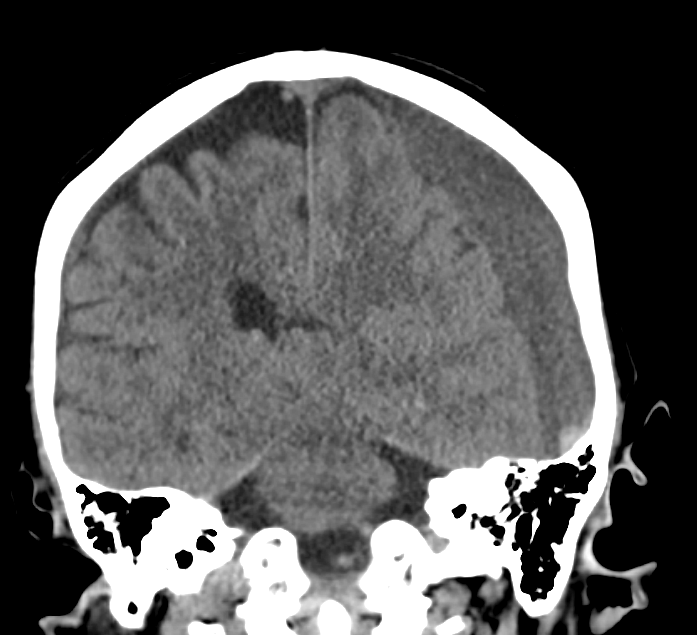

Subdural hematomas are collections of blood between the brain’s tough dural covering and thin arachnoid covering. The most common cause is tearing of venous structures, and it can be caused by minor trauma. Patient’s on anticoagulants, thrombocytopenia or significant cerebral atrophy are at higher risk.

Clues to the presence of subdural hemmorhages include:

- No extension into the sulci (as would be seen in subarachnoid bleeding)

- Concave shape, like a crescent

- Not typically associated with skull fractures, unlike epidural hematomas

- Typically slowly expanding